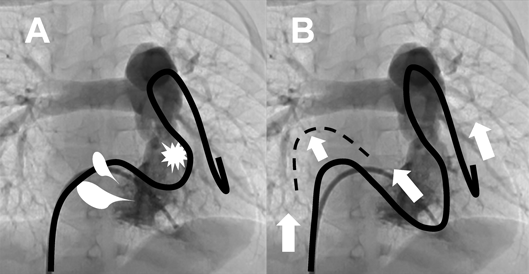

ガイドワイヤー挿入後,親カテーテルを抜去する際にはガイドワイヤー先端が抜けないよう透視下で位置を確認しながらガイドワイヤーを保持して(少し挿入するような感覚で)親カテーテルのみ抜去することが基本手技となる.この際には体外のカテーテルやガイドワイヤーがたわまず直線的になるよう心掛ける.不用意な「たわみ」はガイドワイヤーやカテーテル先端に抜けてくる力が加わるからである.バルーンカテーテルに交換する際はガイドワイヤーをよく濡れたガーゼで湿らせ滑りをよくするとともに血栓等を除去しながら挿入してゆく.この際,バルーンカテーテルとガイドワイヤーの「取り引き」が必要である.主術者一人で操作する時は,左手でバルーンカテーテルのシース側を把持し,右手の人差し指と親指でバルーンカテーテルの尾部を,薬指と小指でガイドワイヤーを把持してガイドワイヤーを少し引き抜く感じで左手と右手でカテーテルを挿入してゆくとよい.助手と協働で行う時は,主術者がバルーンカテーテルを挿入してゆく際,助手はバルーンカテーテルの尾部を左手で,ガイドワイヤーを右手で把持しながら右手のガイドワイヤーを固定してカテーテル尾部を送ってゆくように心がける.この際にも体外のカテーテルとワイヤーが直線状になるよう心掛ける.ガイドワイヤーの挿入が浅かったりシステム全体の支持力が弱いと,屈曲した病変へバルーンカテーテルを挿入する際にガイドワイヤーが抜けてしまうことがあるので,前述のようにガイドワイヤーは病変を超えて十分深く挿入することが重要であるとともに,バルーンカテーテルをあらかじめ体外で「扱いておく」と通過しやすくなる.またバルーンカテーテルのデリバリーに際しシステム全体への過度のテンションは三尖弁や右室流出路の圧迫による血行動態破綻を招くこともあるためガイドワイヤー・カテーテルが自然な位置となるよう常時調節する.また強いテンションのためガイドワイヤーやカテーテルが右房内でS字状となった場合に先端が抜けてくることがあり,焦ってシステムを押すと更に先端が抜けてしまう(Fig. 5).そのため助手は不用意にガイドワイヤーを押し込まないよう注意が必要である.逆にシステムを少し引くことで修正される.症例によっては意図的にループを形成することによりデリバリーシステム全体が安定することもあるので症例ごとにデリバリー方法を工夫することも必要となる.

Pediatric Cardiology and Cardiac Surgery 38(3): 147-157 (2022)

Fig. 5 Pushing a catheter or a guidewire causes tensions to the tricuspid valve and the right ventricular outflow tract, which can elicit hemodynamic incompetence (A). Excessive pushing a guidewire may result in pulling a tip of guidewire (B). Be careful to place a catheter and a guidewire in the neutral position during the procedure.